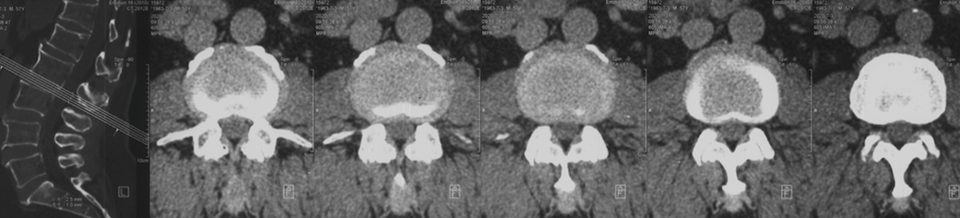

影像资料:

![]()

诊断:

>Scheuermann’s病(II型)

TK=53°>45°

TL=42°>30°

T11/T12/L1楔形变>5°

T12/L1许莫氏结节